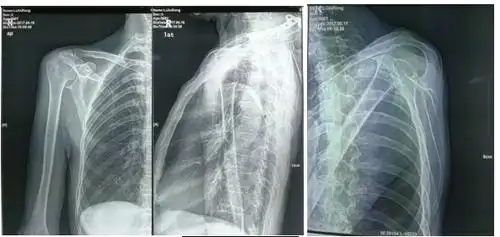

不同肩关节x线投照位

肩关节正位-x线图

肩关节x线检查体位大全